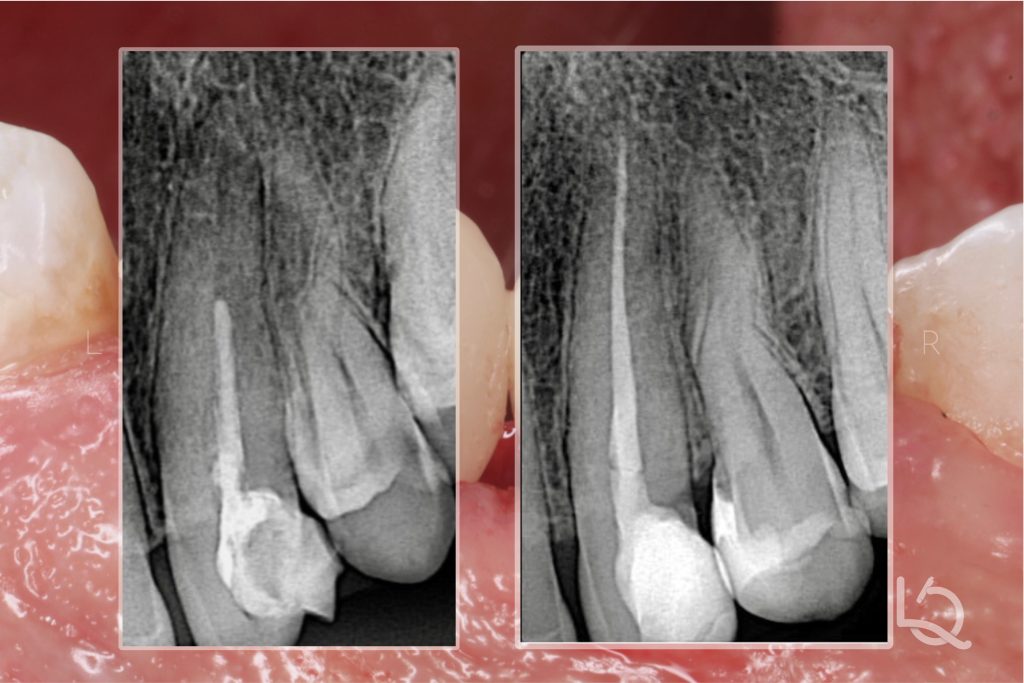

Radiographic examination revealed that the canine had previously undergone root canal treatment (RCT), but the gutta-percha was underfilled by approximately 10 mm.

The final radiograph demonstrates a seamless, “infinite” margin on the mesial surface of the premolar and a well-integrated restoration of the canine, with harmonious contours and tight proximal contact.